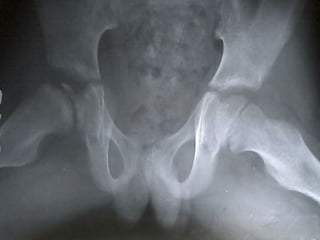

SLIPPED CAPITALSLIPPED CAPITAL

FEMORAL EPIPHYSISFEMORAL EPIPHYSIS

A true adolescent problem

Gradual or acute slip

through the capital

femoral physis

Investigations

X-ray – AP

Frog leg lateral view

( contraindicated when

suspecting acute slip)